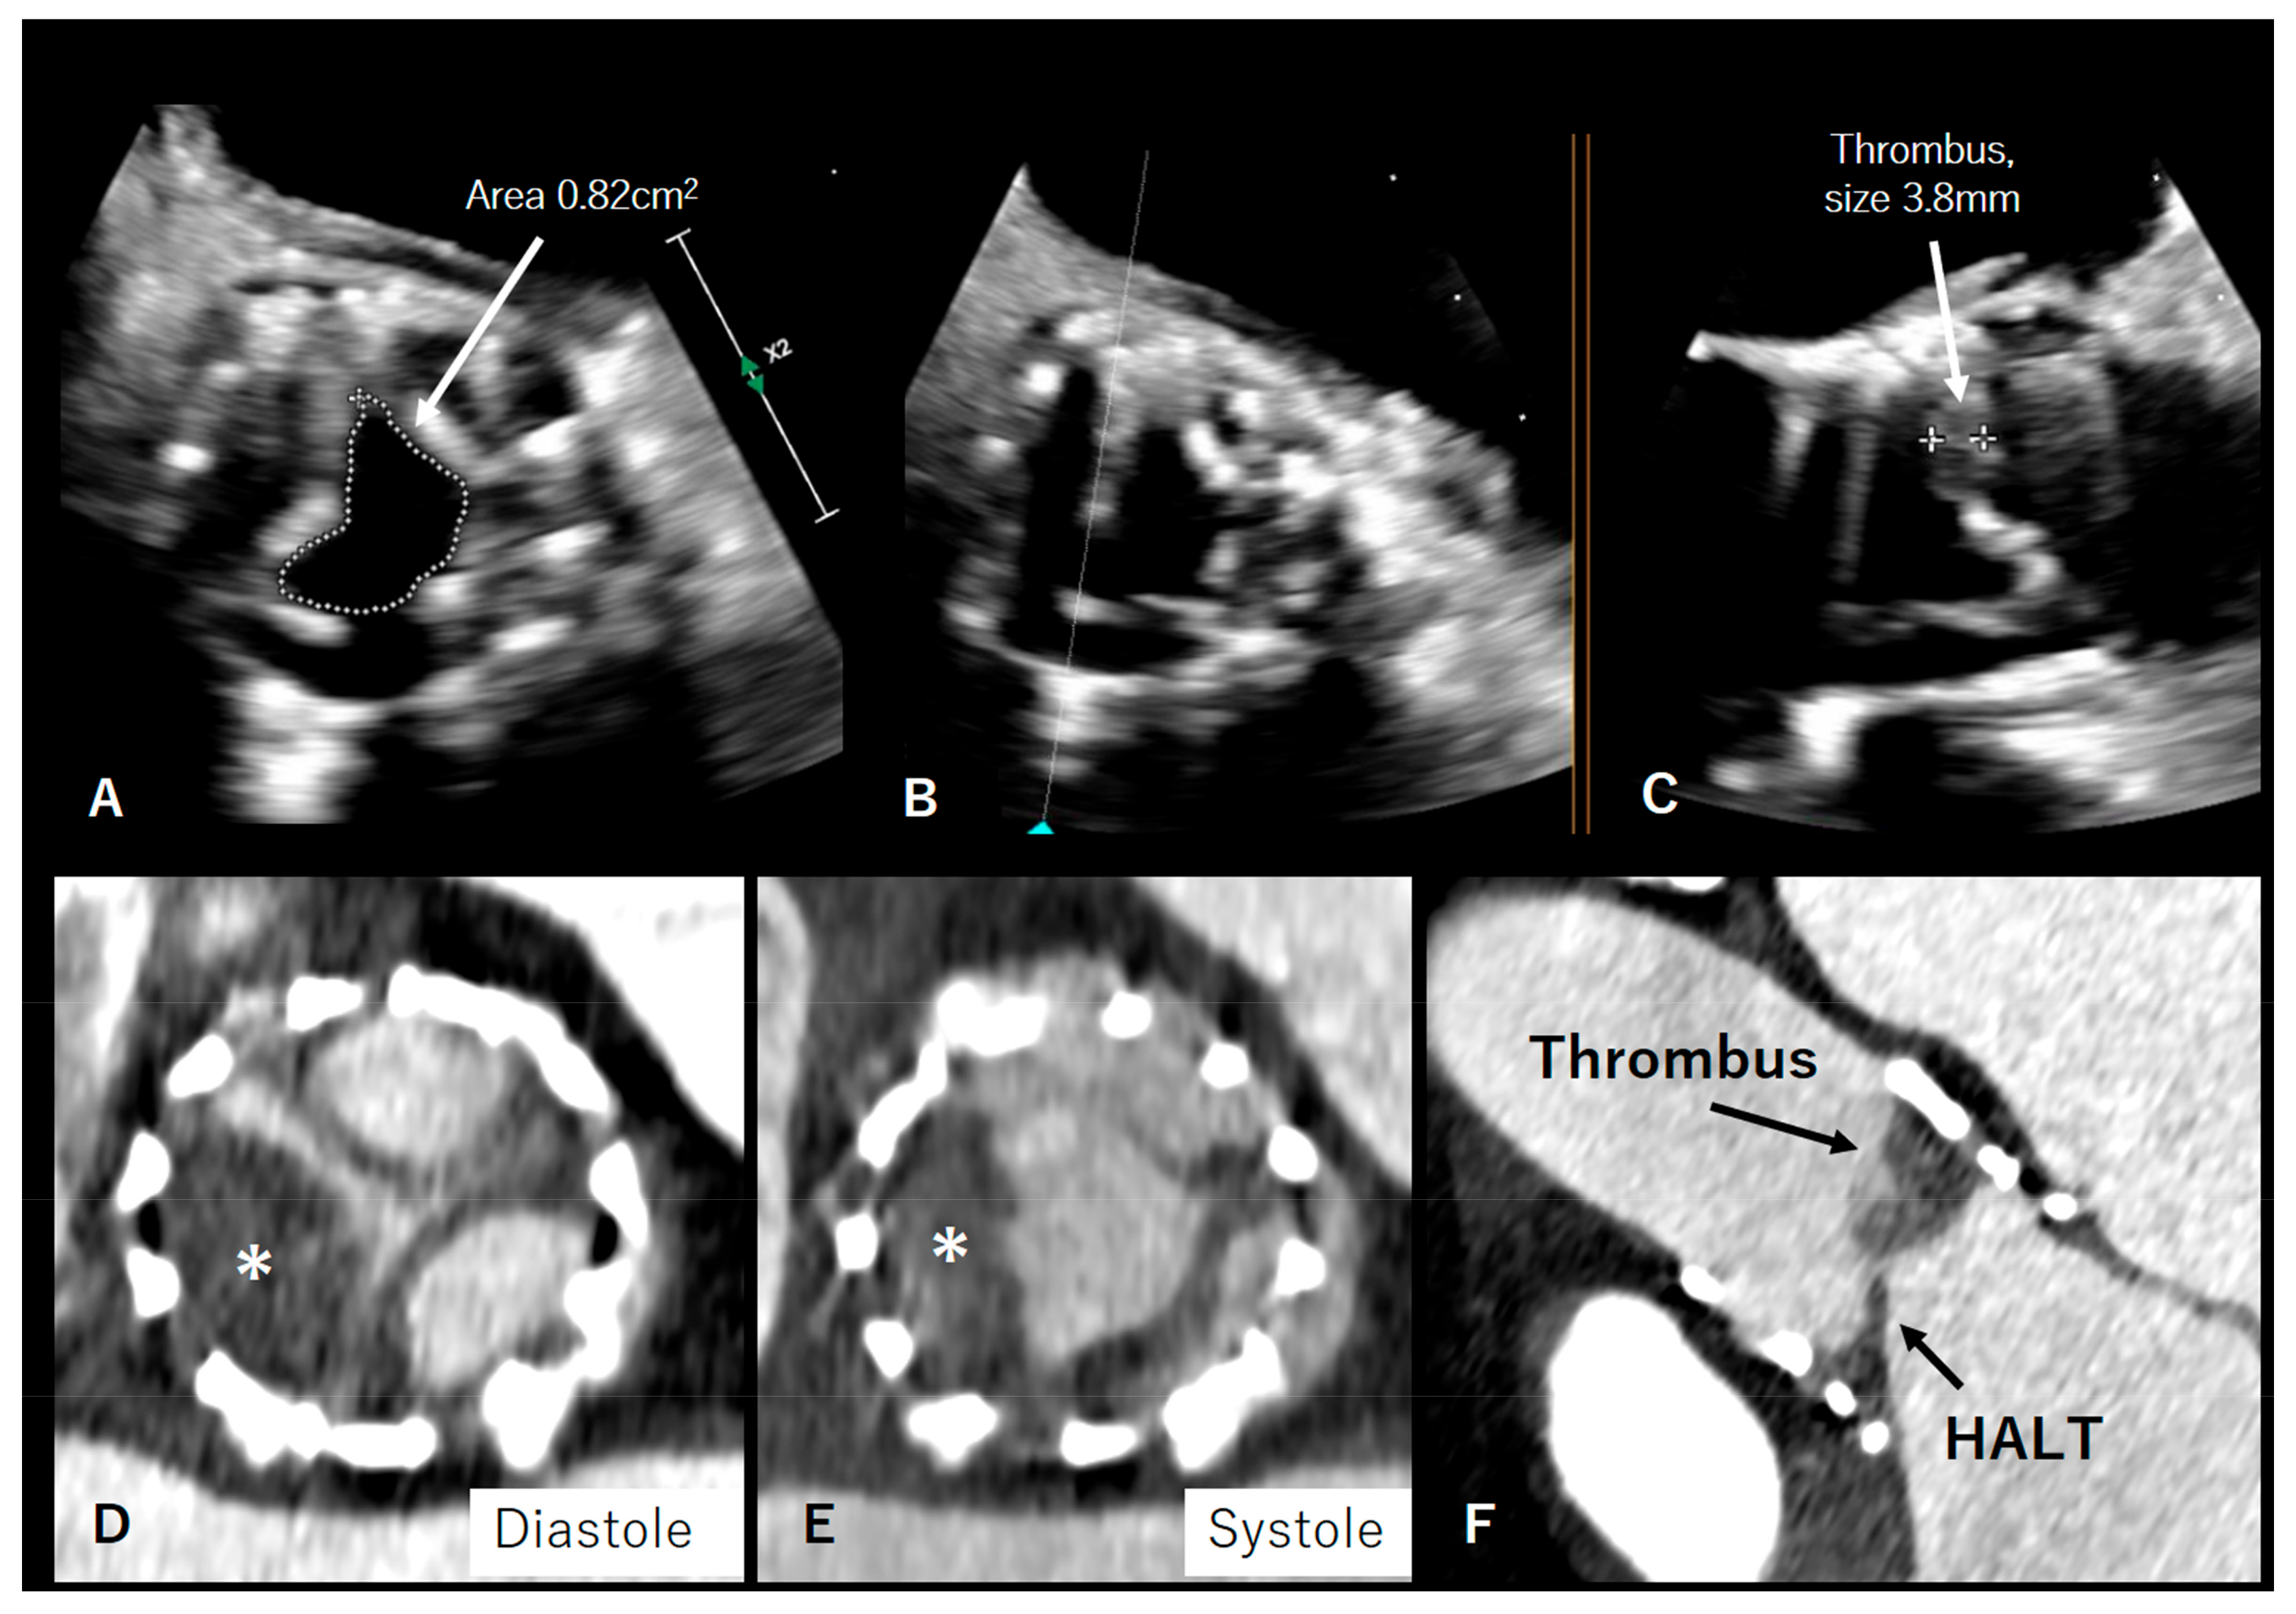

4. Valve Thrombosis/HALT/Pannus